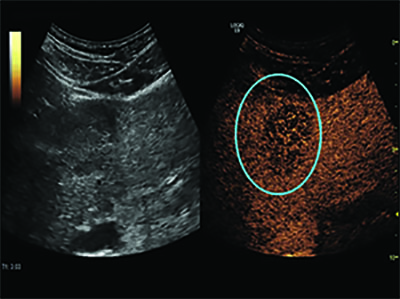

The use of oscillating microbubbles as pressure sensors could also provide early indications of the effectiveness of chemotherapy in treating breast cancer. The approach takes advantage of the fact that interstitial fluid pressure is significantly higher in a tumor than in normal tissue.

A 2017 study in Radiology found that SHAPE was able to predict treatment response in breast cancer patients with 100 percent accuracy after just one round of chemotherapy. (See Web Extras.)

“We see this as an indication that the pressures inside the tumor have dropped, these vessels have opened up and you’re getting more signal in there,” Dr. Forsberg said. “This is an indication that chemotherapy is working.”